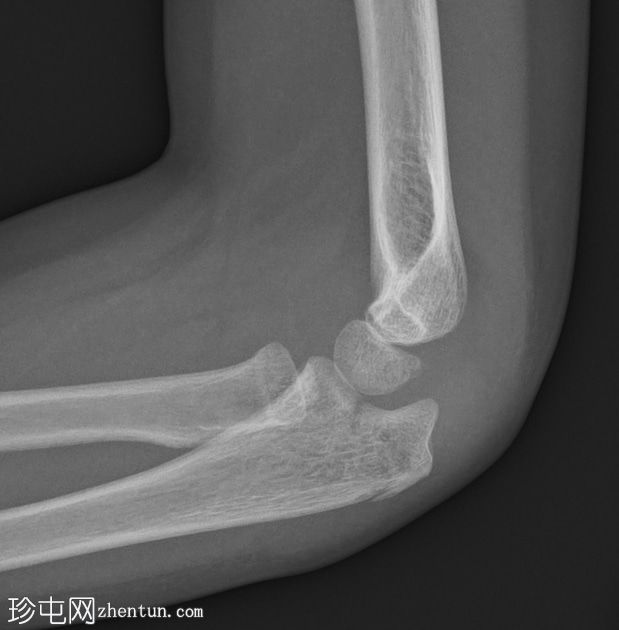

肘关节X线片

侧位片

2.png

可见鹰嘴关节内骨折,桡骨颈轻度移位骨折,侧位片可见轻微硬化。肘关节对位良好。关节积液,表现为前后脂肪垫抬高。

儿科,桡骨颈骨折比桡骨头骨折更常见(与成人相反)。如本例所示,桡骨颈骨折通常表现隐匿,轻微硬化或轻度成角可能是唯一的体征。

鹰嘴骨折虽然不常见,但容易被忽略,因此是常见的漏诊骨折。侧位片通常最有帮助。

务必始终评估关节对位情况。如果存在桡骨小头关节脱位,则该损伤属于蒙特吉亚骨折脱位。描述关节对位正常非常重要。